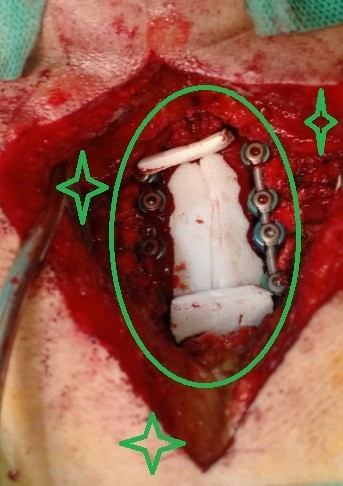

مريض 55 عام يعاني من ضعف بالجانب الأيمن بالجسم وخذل بالأطراف الأربعة مع تيبس اثناء الحركة ناتج عن اصابته بضيق شديد بالفقرات العنقية مع تحدب للأمام بالفقرات العنقية. تم علاجه عن طريق اجراء جراحة لتوسيع مجري القناة العصبية العنقية وتركيب نظام تثبيت خلفي لإصلاح التحدب وتثبيت الفقرات العنقية. كما هو واضح من صور اشعة الرنين قبل الجراحة وصور النخاع بعد رفع الضغط عنه ووضع نظام التثبيت وصور الاشعة المقطعية بعد المتابعة.

تم إجراء جراحة ناجحة للتوسيع الخلفي وتثبيت الفقرات العنقية. هذا الإجراء المتخصص يهدف إلى علاج الضغط على الحبل الشوكي في منطقة الرقبة، والذي ينتج عن تضيق القناة الشوكية أو عدم استقرار الفقرات العنقية.